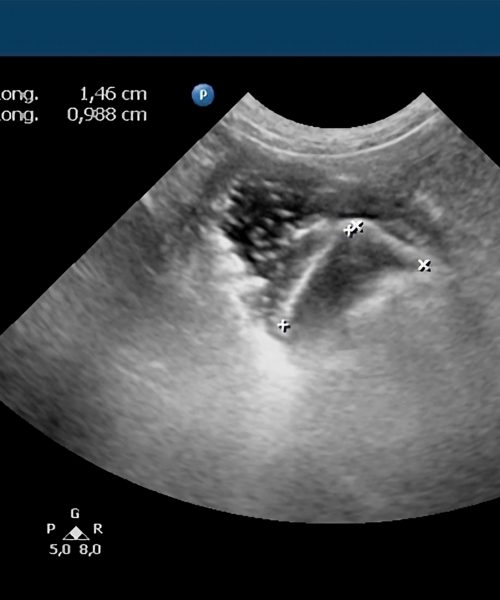

Valido la precisión diagnóstica comparando las imágenes ecográficas con los hallazgos quirúrgicos reales.

Garantizo transparencia y confianza exhibiendo en este apartado casos reales con su correlación intraoperatoria documentada.